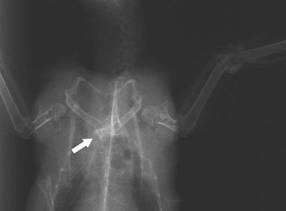

Fracture of the

clavicula and the coracoid: multiple

fractures happen

frequently during flying onto

something

The fatal luxatio

art. sternocoracoidea is not easily recognisable in the

normal ventrodorsal x-ray. When the wing is stretched, the

connected separation coracoid-sternum is hardly noticeable |

Luxatio art.

sternocoracoidea: not until the provocation x-ray (pushing

together of the wings to the median) is the shift of the

coracoid across the middle line visible

The shoulder girdle

defects occurring most frequently are fractures of the clavicula and

the coracoid as well as the luxatio articulatio humeri (shoulder

luxation), which clinically shows itself in the same way and can be

clearly diagnosed in the x-ray: the very often significant

dislocation of the upper arm as well as the clearly enlarged

distance between the humerus head and shoulder joint of the side

concerned are visible. It is harder to diagnose luxatio art.

sternocoracoidea, which is not so infrequent: the sinewy attachment

of the coracoid to the breastbone is torn off with a dislocation

beyond the median. This defect can easily be overlooked on the x-ray

and requires a trained eye.